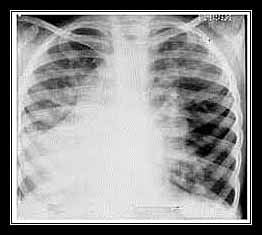

2. BỆNH PHỔI – PHẾ QUẢN NHIỄM KHUẨN với nhiều ổ rải rác trong hai phế trường:

6. BỆNH PHỔI – MÀNG PHỔI NHIỄM TỤ CẦU:

có hình bong bóng ở phổi và chướng bụng